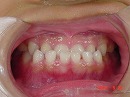

初診時 終了時

もし、初診時の様なかみ合わせで成長をつづけた場合を想像してみましょう。

将来の歯並びはどの様な状態となっている事でしょうか…?

早期に治療を開始することによって、

良好な歯並び、かみ合わせを維持しやすくなります。